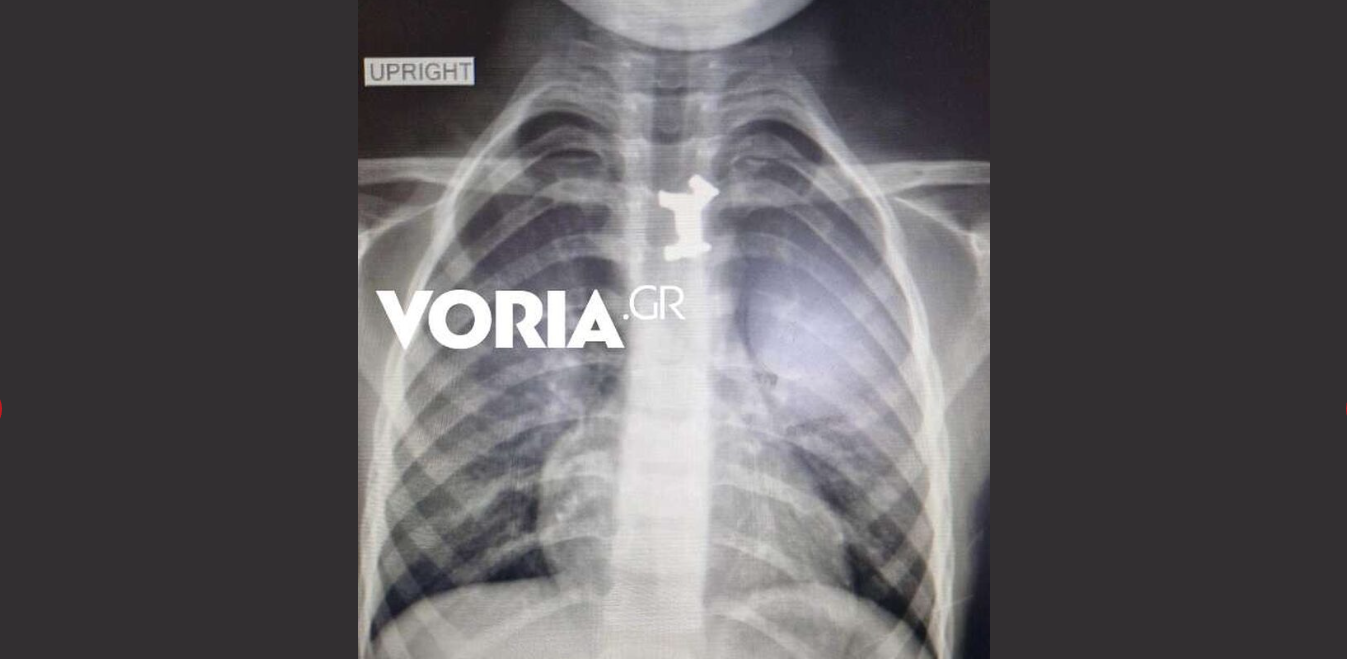

Όπως αναφέρει το Voria.gr, μετά από τις ακτινογραφίες και τις απεικονιστικές εξετάσεις διαπιστώθηκε πως το παιδί είχε καταπιεί ένα μεταλλικό σκυλάκι (!) από γνωστό επιτραπέζιο παιχνίδι που έπρεπε να αφαιρεθεί άμεσα, καθώς ήταν σε αρκετά δύσκολο σημείο.

Αφότου έγιναν όλες οι απαραίτητες εξετάσεις για τον ακριβή εντοπισμό του αντικειμένου, αλλά και μετά από εκτίμηση παιδο-ΩΡΛ, υπεβλήθη σήμερα το πρωί σε οισοφαγοσκόπηση -πρόκειται για μέθοδο αντιμετώπισης οξέων αποφράξεων του ανώτερου πεπτικού στα παιδιά- υπό γενική αναισθησία για την αφαίρεσή του από τον οισοφάγο.